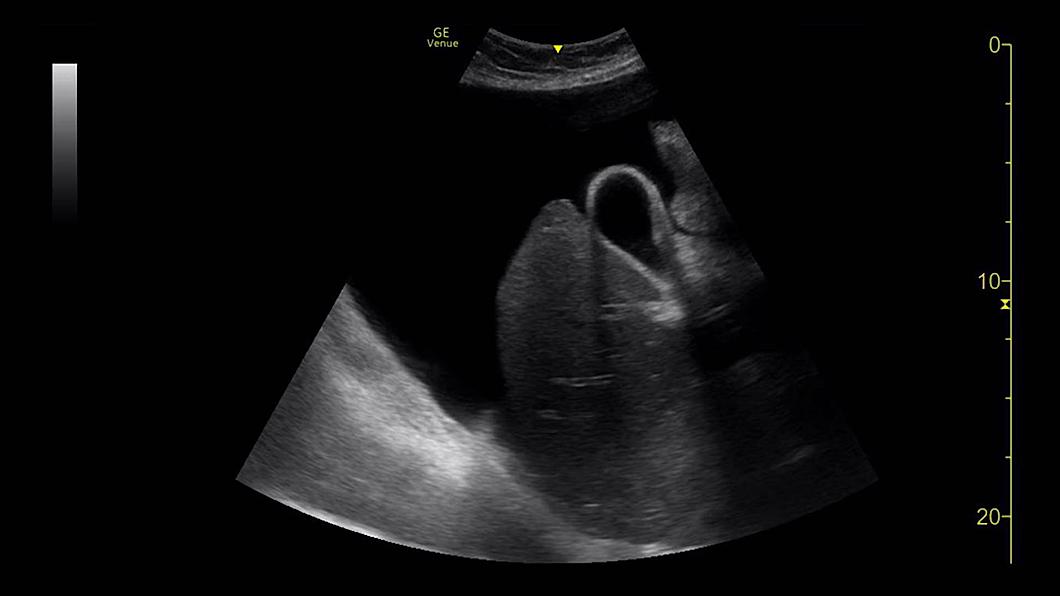

Images cliniques

Des outils d’imagerie conçus pour la réanimation